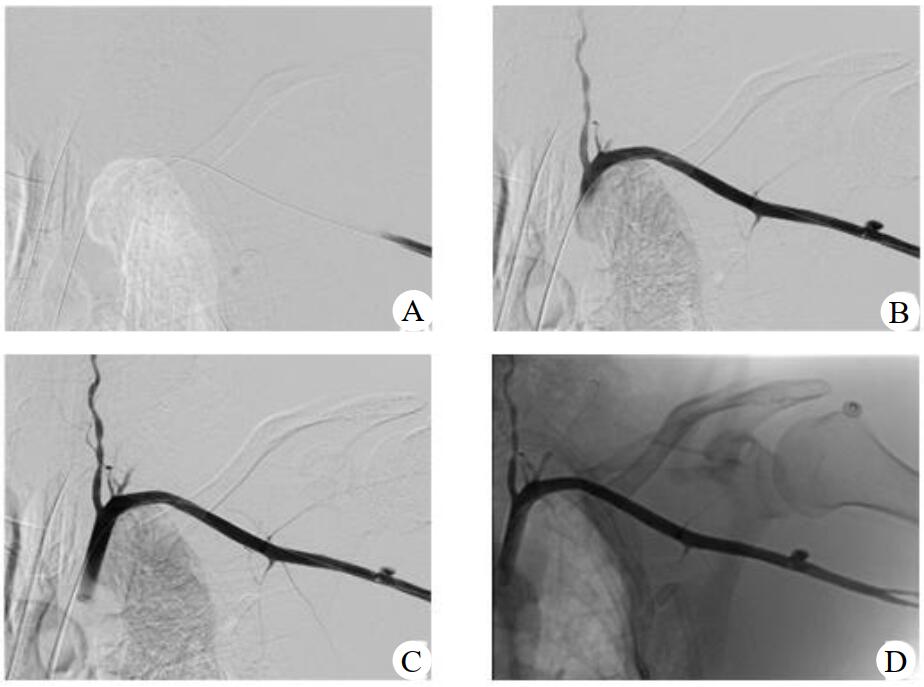

血管外科行左腋动脉造影和左腋动脉覆膜支架植入术,术中造影见左腋动脉破裂伴造影剂外渗,在三维路图引导下将带有导送装置的覆膜支架(8 mm×5 cm,GORE VIABAHN,美国)送入腋动脉,将支架中点覆盖血管破口后释放支架,再次造影见腋动脉通畅,无造影剂外渗,见图 2。

| A、B:左腋动脉造影可见造影剂外溢;C、D:置入覆膜支架后造影剂无外渗 图 2 左腋动脉造影和左腋动脉覆膜支架植入术 |

创伤性腋动脉破裂出血是一种临床少见、致死率高的肩部损伤,临床上发生率极低。腋动脉自身的创伤性损伤仅为主动脉损伤的2.9%~9%[1]。腋动脉损伤常常继发于上肢关节脱位,与下肢相比,其发生率不足1%[2]。因腋动脉位置隐匿,临床表现无明显特异性,易引起忽视。Kelley等[3]认为,当患者存在肩关节外伤史,动脉彩色多普勒超声检查发现存在动脉血流变化以及不断增大的腋窝肿块即可及时诊断腋动脉损伤。本病例血管造影可见左侧腋动脉起始部造影剂外渗,在置入覆膜支架后腋动脉显影通畅,无造影剂外溢现象,术后行三维重建可见支架影。